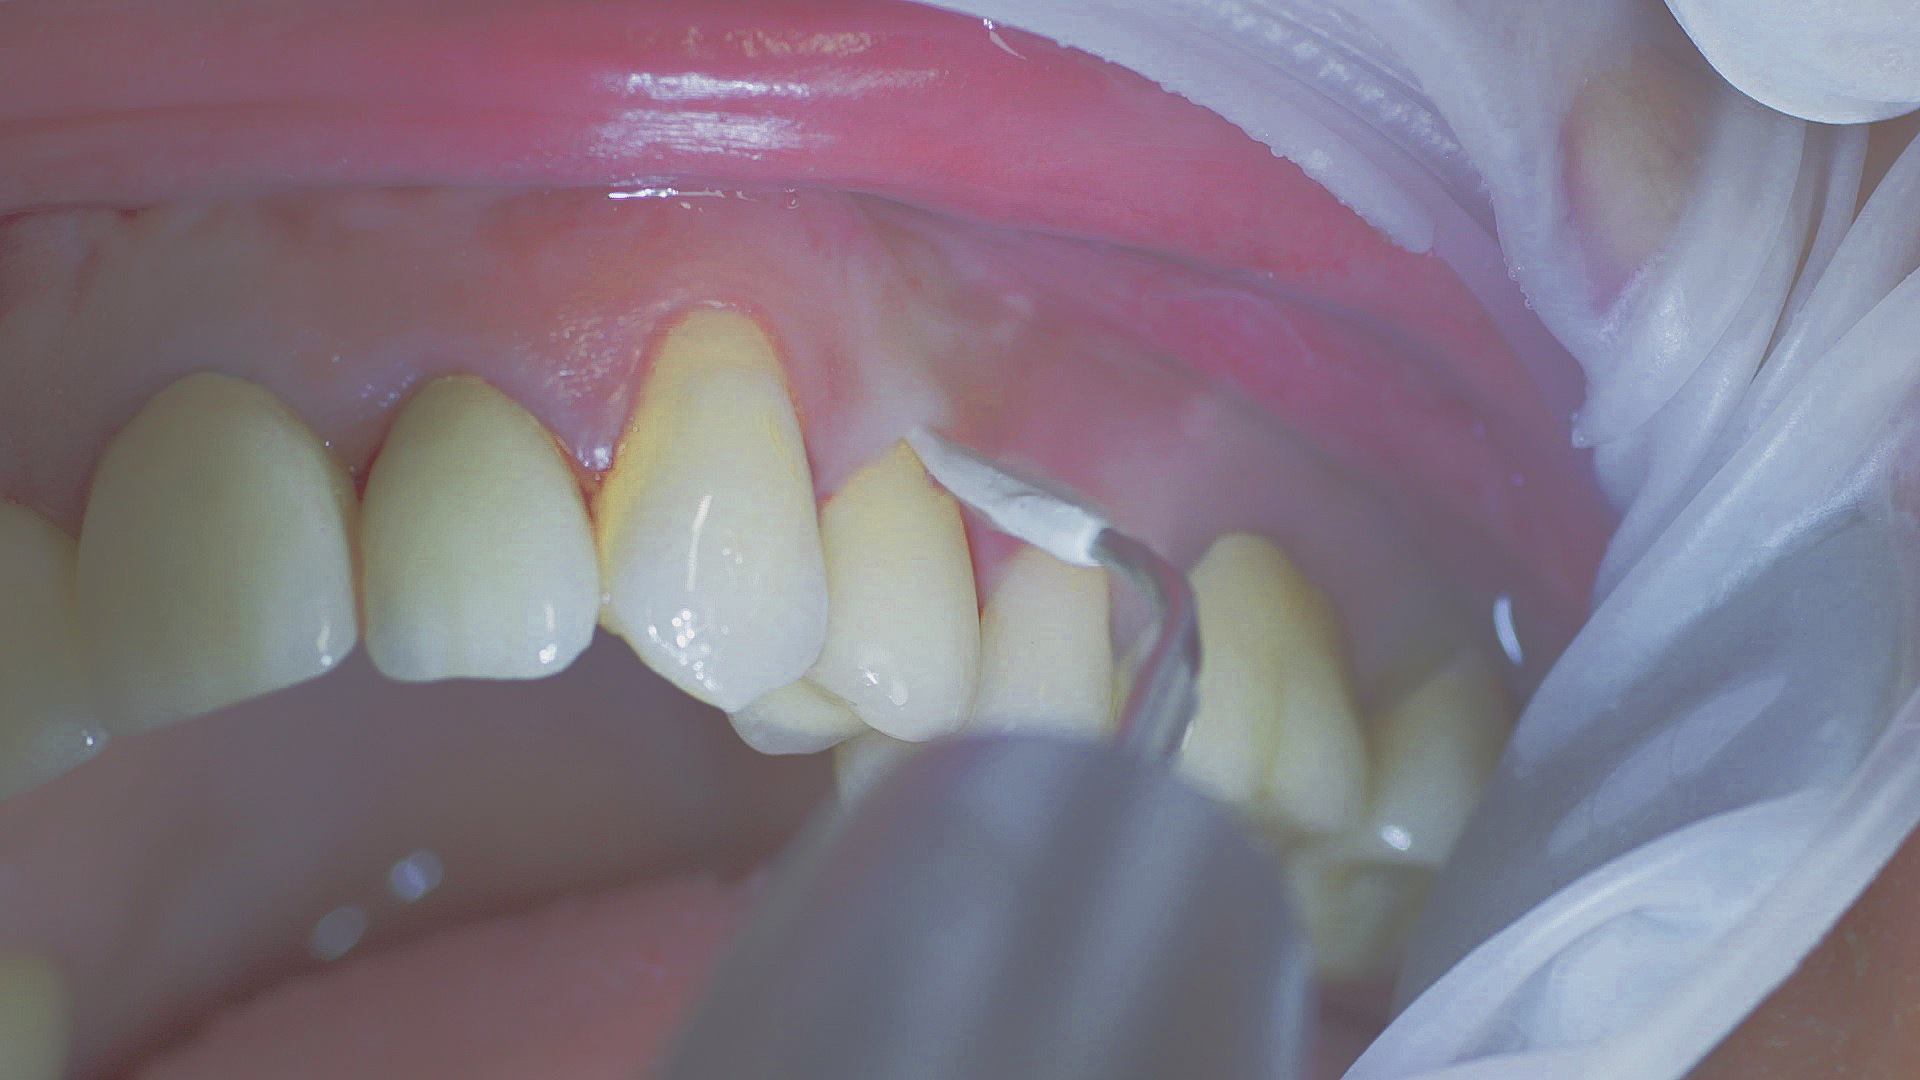

Implants and superstructures can be successfully cleaned with ultrasonic devices and special plastic instruments

Fig. 3: Implants and superstructures can be successfully cleaned with ultrasonic devices and special plastic instruments during postoperative care or non-surgical therapy.

Healthy peri-implant tissue does not show any signs of redness, swelling or bleeding, neither does it secrete pus when probed.[5] Based on the consensus document, Prof. Giovanni Salvi explained the importance of regu- lar probing — preferably with a flexible probe, as implant components often tend to obstruct the procedure.[5] In the case of mucositis or initial peri-implantitis already being present, the non-surgical removal of hard deposits and biofilm should be attempted first. For this purpose, ultra- sonic power and special instruments designed to protect the implant should be employed (Fig. 3; piezo scaler Tigon+ with 1I, W&H). In case of no remission, the recall frequency needs to be increased. However, specific recommendations, applicable to individual cases, are not yet available in this context.[15]